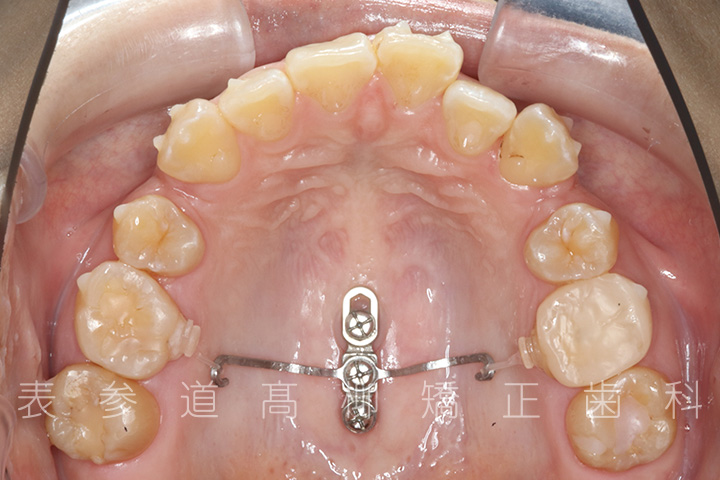

・マウスピース型矯正装置と歯科矯正用アンカースクリュー(i-station)を併用し、上顎臼歯部を圧下

・歯科矯正用アンカースクリュー(i-station)を併用し、前歯部を後方へ移動する

・歯科矯正用アンカースクリューを併用し、口下顎大臼歯の近心移動(前方への移動)